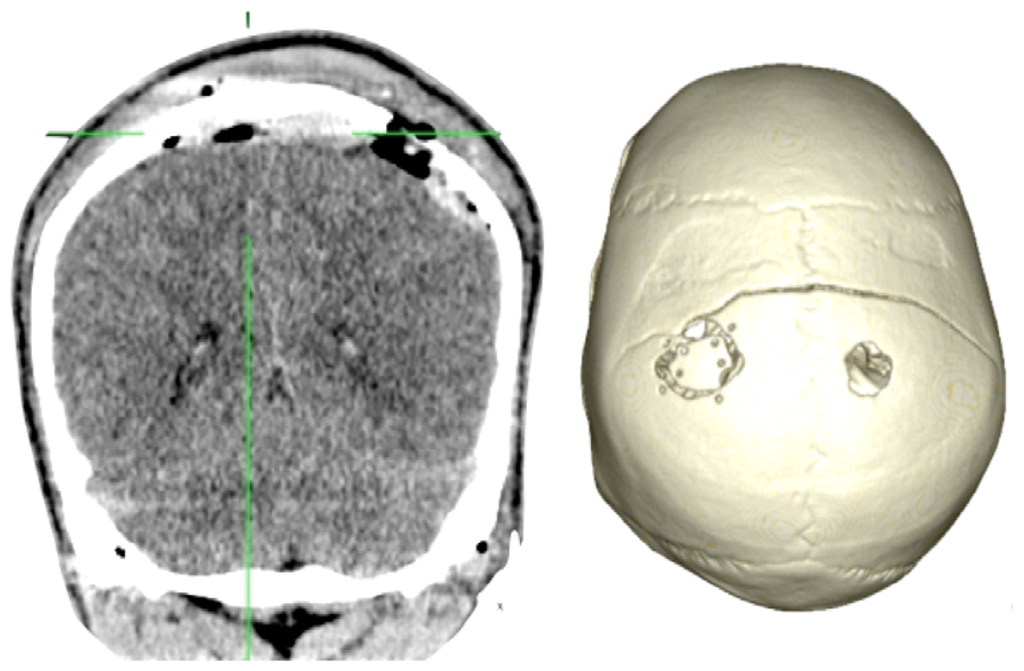

Case 1-Epidural Hematoma (See Figures 1 and 2 for the details)

A 48-year-old male patient experienced traumatic brain injury due to fall from a height of 3 m. Initial loss of consciousness was noted, but the patient remained conscious and alert after the insult. He went home and was found drowsy by a family member. He was then brought to our emergency department (GCS of 14), where head CT scan revealed a bilateral parietal EDH (40 mL in volume).

The 3D reconstruction enabled a minimally invasive approach to this case. A linear incision was made at the site where the center of the hematoma is located, and a 2.5-cm diameter craniotomy was created. Another 1.5 cm incision and 1 cm burr-hole was performed in the contralateral side, leaving the hematoma beneath the superior sagittal sinus untouched. After surgery the patient had an excellent recovery with no neurological deficits. He was discharged three days after admission to the hospital.

We have used a minimally invasive approach for patients with epidural hematomas. The idea was to place a small craniotomy at the center of the hematoma, and the craniotomy diameter was half the overall diameter of the hematoma. Thus, it was possible to make only small straight incisions (mean 3.5 cm). The average diameter of hematomas was 6 cm and the mean of the volumes of hematomas was 31.5 mL. The vast majority of patients had a favorable outcome, as is to be expected in patients with uncomplicated epidural hematomas.